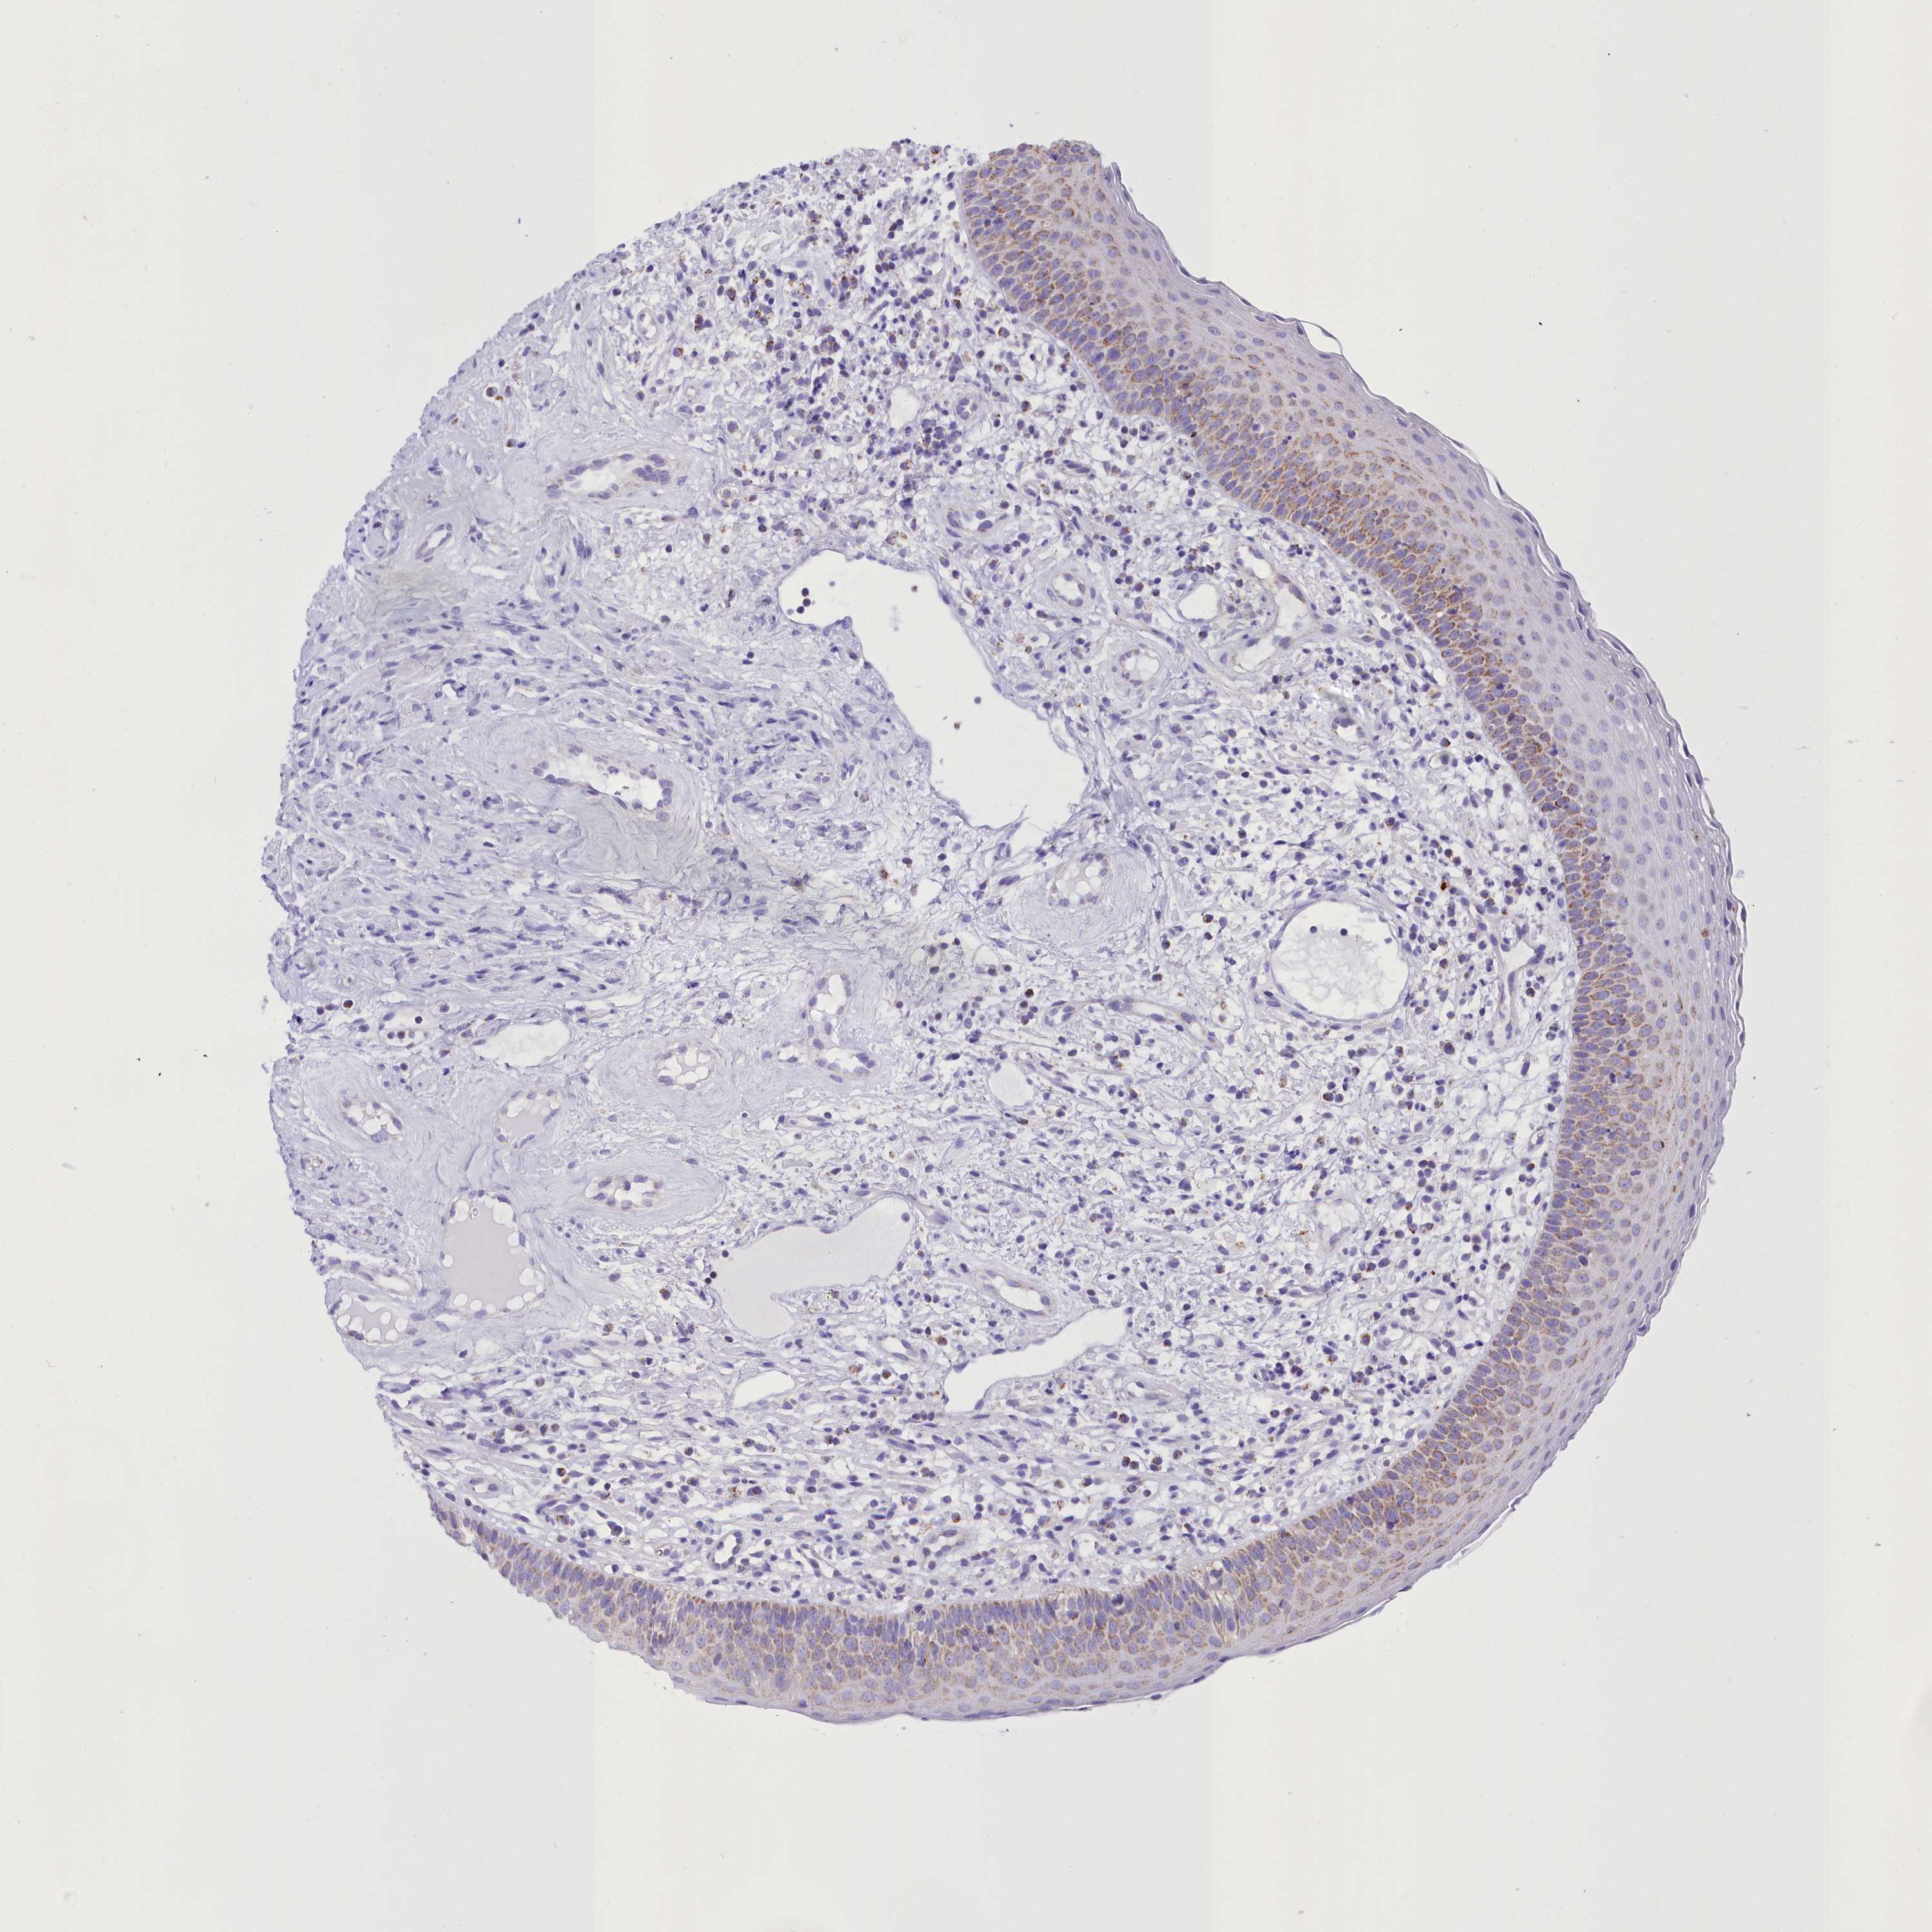

WDFY3